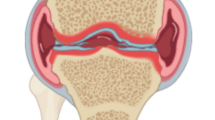

Osteoarthritis was induced by anterior cruciate ligament transection of the right knee in crossbred dogs. There were two treatment groups (n = 8 dogs/group), in which the animals received either placebo or avocado/soybean unsaponifiables (10 mg/kg per day), which were given orally for the entire duration of the study (8 weeks). We conducted macroscopic and histomorphological analyses of cartilage and subchondral bone of the femoral condyles and/or tibial plateaus. We also conducted immunohistochemical analyses in cartilage for the following antigens: inducible nitric oxide synthase, matrix metalloproteinase (MMP)-1, MMP-13, a disintegrin and metalloproteinase domain with thrombospondin motifs (ADAMTS)4 and ADAMTS5.

Full thickness cartilage sections were removed from the weight-bearing lesional areas of the femoral condyles and tibial plateaus, allowing standardization of sampling as recommended by the OA Research Society International guidelines [15]. Histological evaluation was performed on sagittal sections of cartilage removed from each femoral condyle and tibial plateau specimen [16]. Specimens were dissected, fixed in TissuFix #2 (Laboratoires Gilles Chaput, Montreal, QC, Canada) and embedded in paraffin for histological evaluation. Serial sections (5 μm) were stained with Safranin-O. Two independent observers (CB and JC), who were blinded to treatment group allocation, graded the severity (consensus score) of the OA lesions in each cartilage section, which was divided into three subregions [15], on a scale of 0 to 29, modified from that reported by Sakakibara and colleagues [17]. This scale was used to evaluate the severity of OA lesions based on the loss of Safranin-O staining (scale 0 to 4), cellular changes (scale 0 to 12), structural changes (scale 0 to 10, where 0 = normal cartilage structure and 10 = complete disorganization) and pannus formation (scale 0 to 3). The final score (range 0 to 87) corresponds to the sum of the final scores for the three subregions of each specimen from the femoral condyle or tibial plateau.

Subchondral bone and calcified cartilage histomorphometry

Specimens of full-thickness sections, which included the calcified cartilage and subchondral bone, were removed from the OA knee of all dogs and were placed in 70% ethanol and further decalcified with rapid bone decalcifier (RDO; Apex Engineering, Aurora, IL, USA). Specimens were embedded in paraffin for the purpose of histomorphometric analysis.

Sections (5 μm) of each specimen were subjected to hematoxylin/eosin staining. A Leitz Diaplan microscope (Leica Microsystems, Wetzlar, Germany) connected to a personal computer (Pentium IV based, using OSTEO II Image Analysis Software [Bioquant, Nashville, TN, USA]) was used to conduct bone histomorphometry analysis.

Subchondral bone histomorphometry was performed on three nonconsecutive sections of each specimen using our previously published method [18], modified from that of Matsui and coworkers [19]. The calcified cartilage/subchondral bone junction was used as the upper limit of each field. The depth was measured from the upper limit to 2,000 μm. Measurement of the bone surface (% of tissue surface) and trabecular thickness (μm) followed standard conventions, as previously described [18]. The measurement of the fields was then averaged for each section. Values for each section were considered separately for the purposes of statistical analysis.

Calcified cartilage histomorphometry was also done on three nonconsecutive sections of each specimen, as previously described [18]. From each section, three representative fields of 1,000 μm length (original magnification ×60) were selected. The tidemark/cartilage and calcified cartilage/bone junctions were used as upper and lower limits. The mean thickness (mm) of the calcified cartilage was calculated. The measurement made in the three fields was then averaged for each section and the value of each section was considered separately.

Bone histomorphometric analysis

Bone surface was 75.9% (50.8% to 86.2%; median [range]) of the tissue surface in the placebo group compared with 79.3% (66.0% to 90.8%; P < 0.05) in the ASU-treated group (Figure 3). Trabecular thickness did not differ between the ASU (132.3 μm [102.8 μm to 200.5 μm]) and placebo (129.1 μm [90.0 μm to 156.0 μm]) groups.

Subchondral bone and calcified cartilage. Representative sections and data of placebo-treated and ASU-treated dogs 8 weeks post-surgery (original magnification ×100). Sections were stained with haematoxylin/eosin. Data for bone volume and calcified cartilage thickness are represented as box plot and were analyzed using Student's unpaired t-test. P ≤ 0.05 is considered significant. ASU, avocado/soybean unsaponifiables.

The calcified cartilage thickness was significantly greater in the ASU group (102.9 μm [85.5 μm to 138.7 μm]) than in the placebo group (91.2 μm [55.2 μm to 145.9 μm]; P = 0.01).